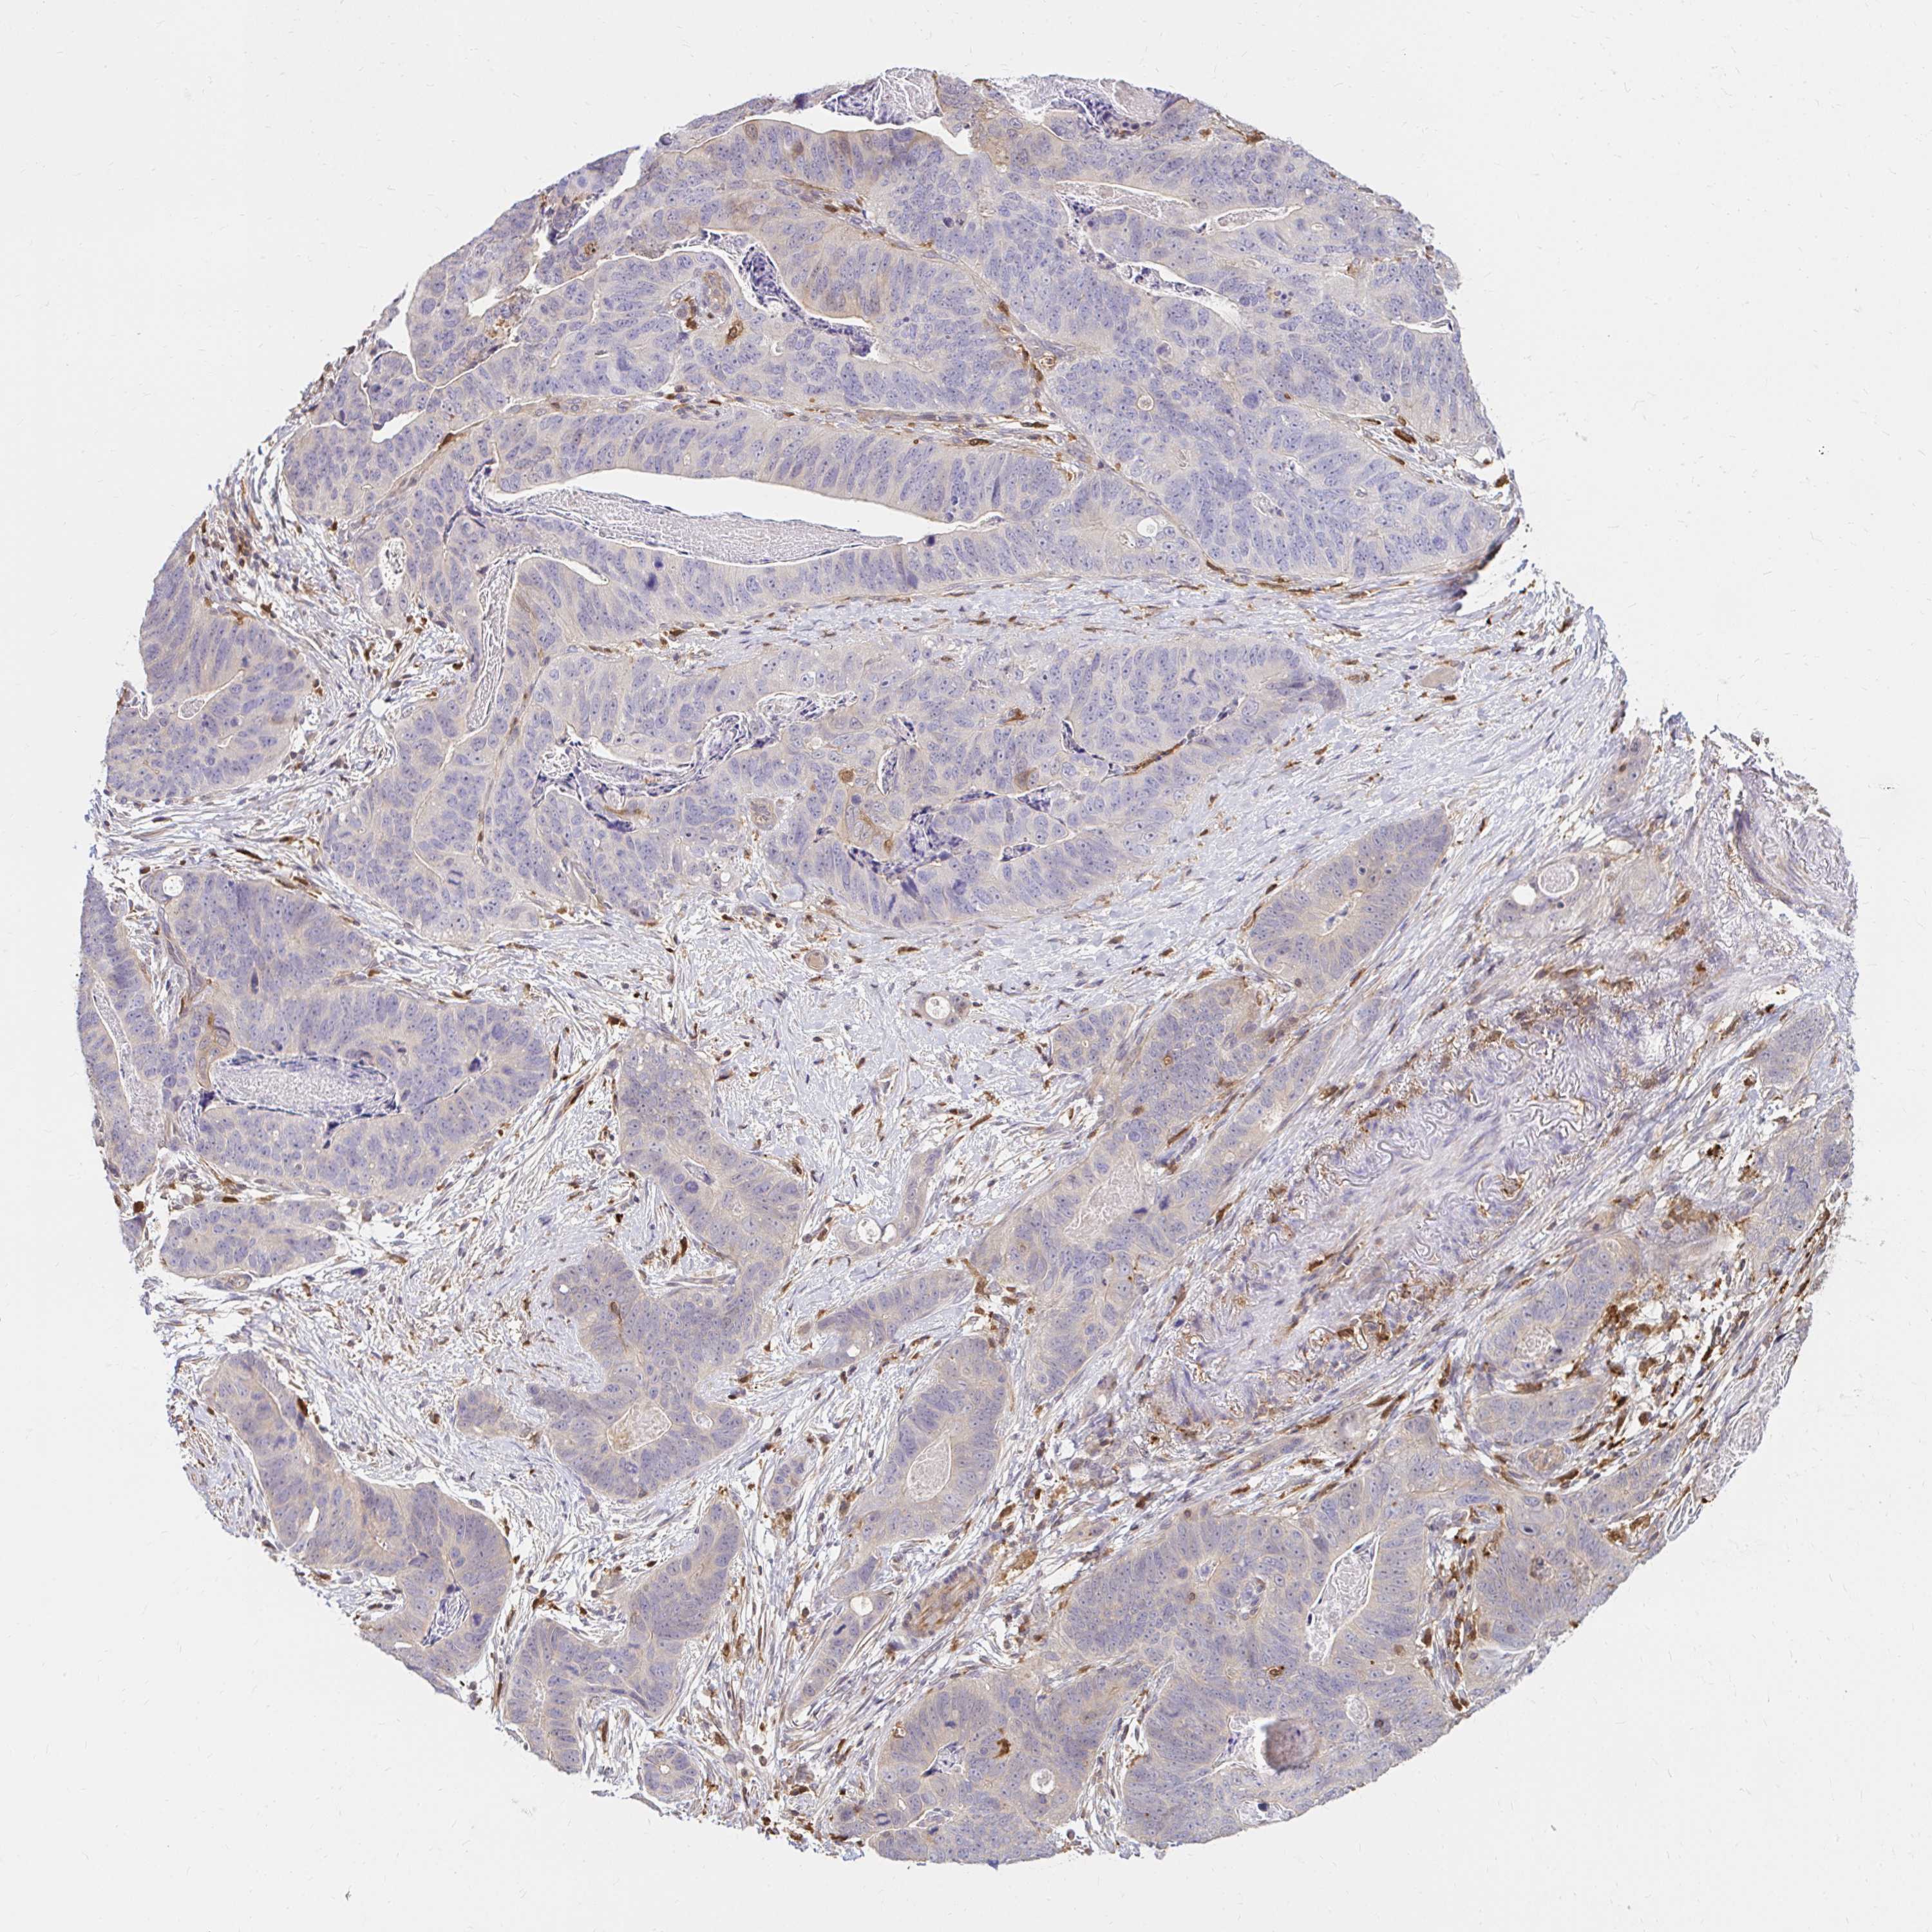

STOMACH CANCER - Protein expressioni

A mouse-over function shows sample information and annotation data. Click on an image to view it in a full screen mode. Samples can be filtered based on level of antibody staining by selecting one or several of the following categories: high, medium, low and not detected. The assay and annotation is described here.

Note that samples used for immunohistochemistry by the Human Protein Atlas do not correspond to samples in the TCGA dataset.

Antibody stainingi

Antibody staining in the annotated cell types in the current human tissue is reported as not detected, low, medium, or high, based on conventional immunohistochemistry profiling in selected tissues. This score is based on the combination of the staining intensity and fraction of stained cells.

Each image is clickable and will lead to virtual microscopy that enables deeper exploration of all samples and also displays staining intensity scores, fraction scores and subcellular localization as well as patient and tissue information for each sample.

Antibody CAB006853

Staining

High

Medium

Low

Not detected

Intensity

Strong

Moderate

Weak

Negative

Quantity

>75%

75%-25%

<25%

None

Location

Nuclear

Cytoplasmic/membranous

Cytoplasmic/membranous,nuclear

Adenocarcinoma, NOS

Adenocarcinoma, High grade